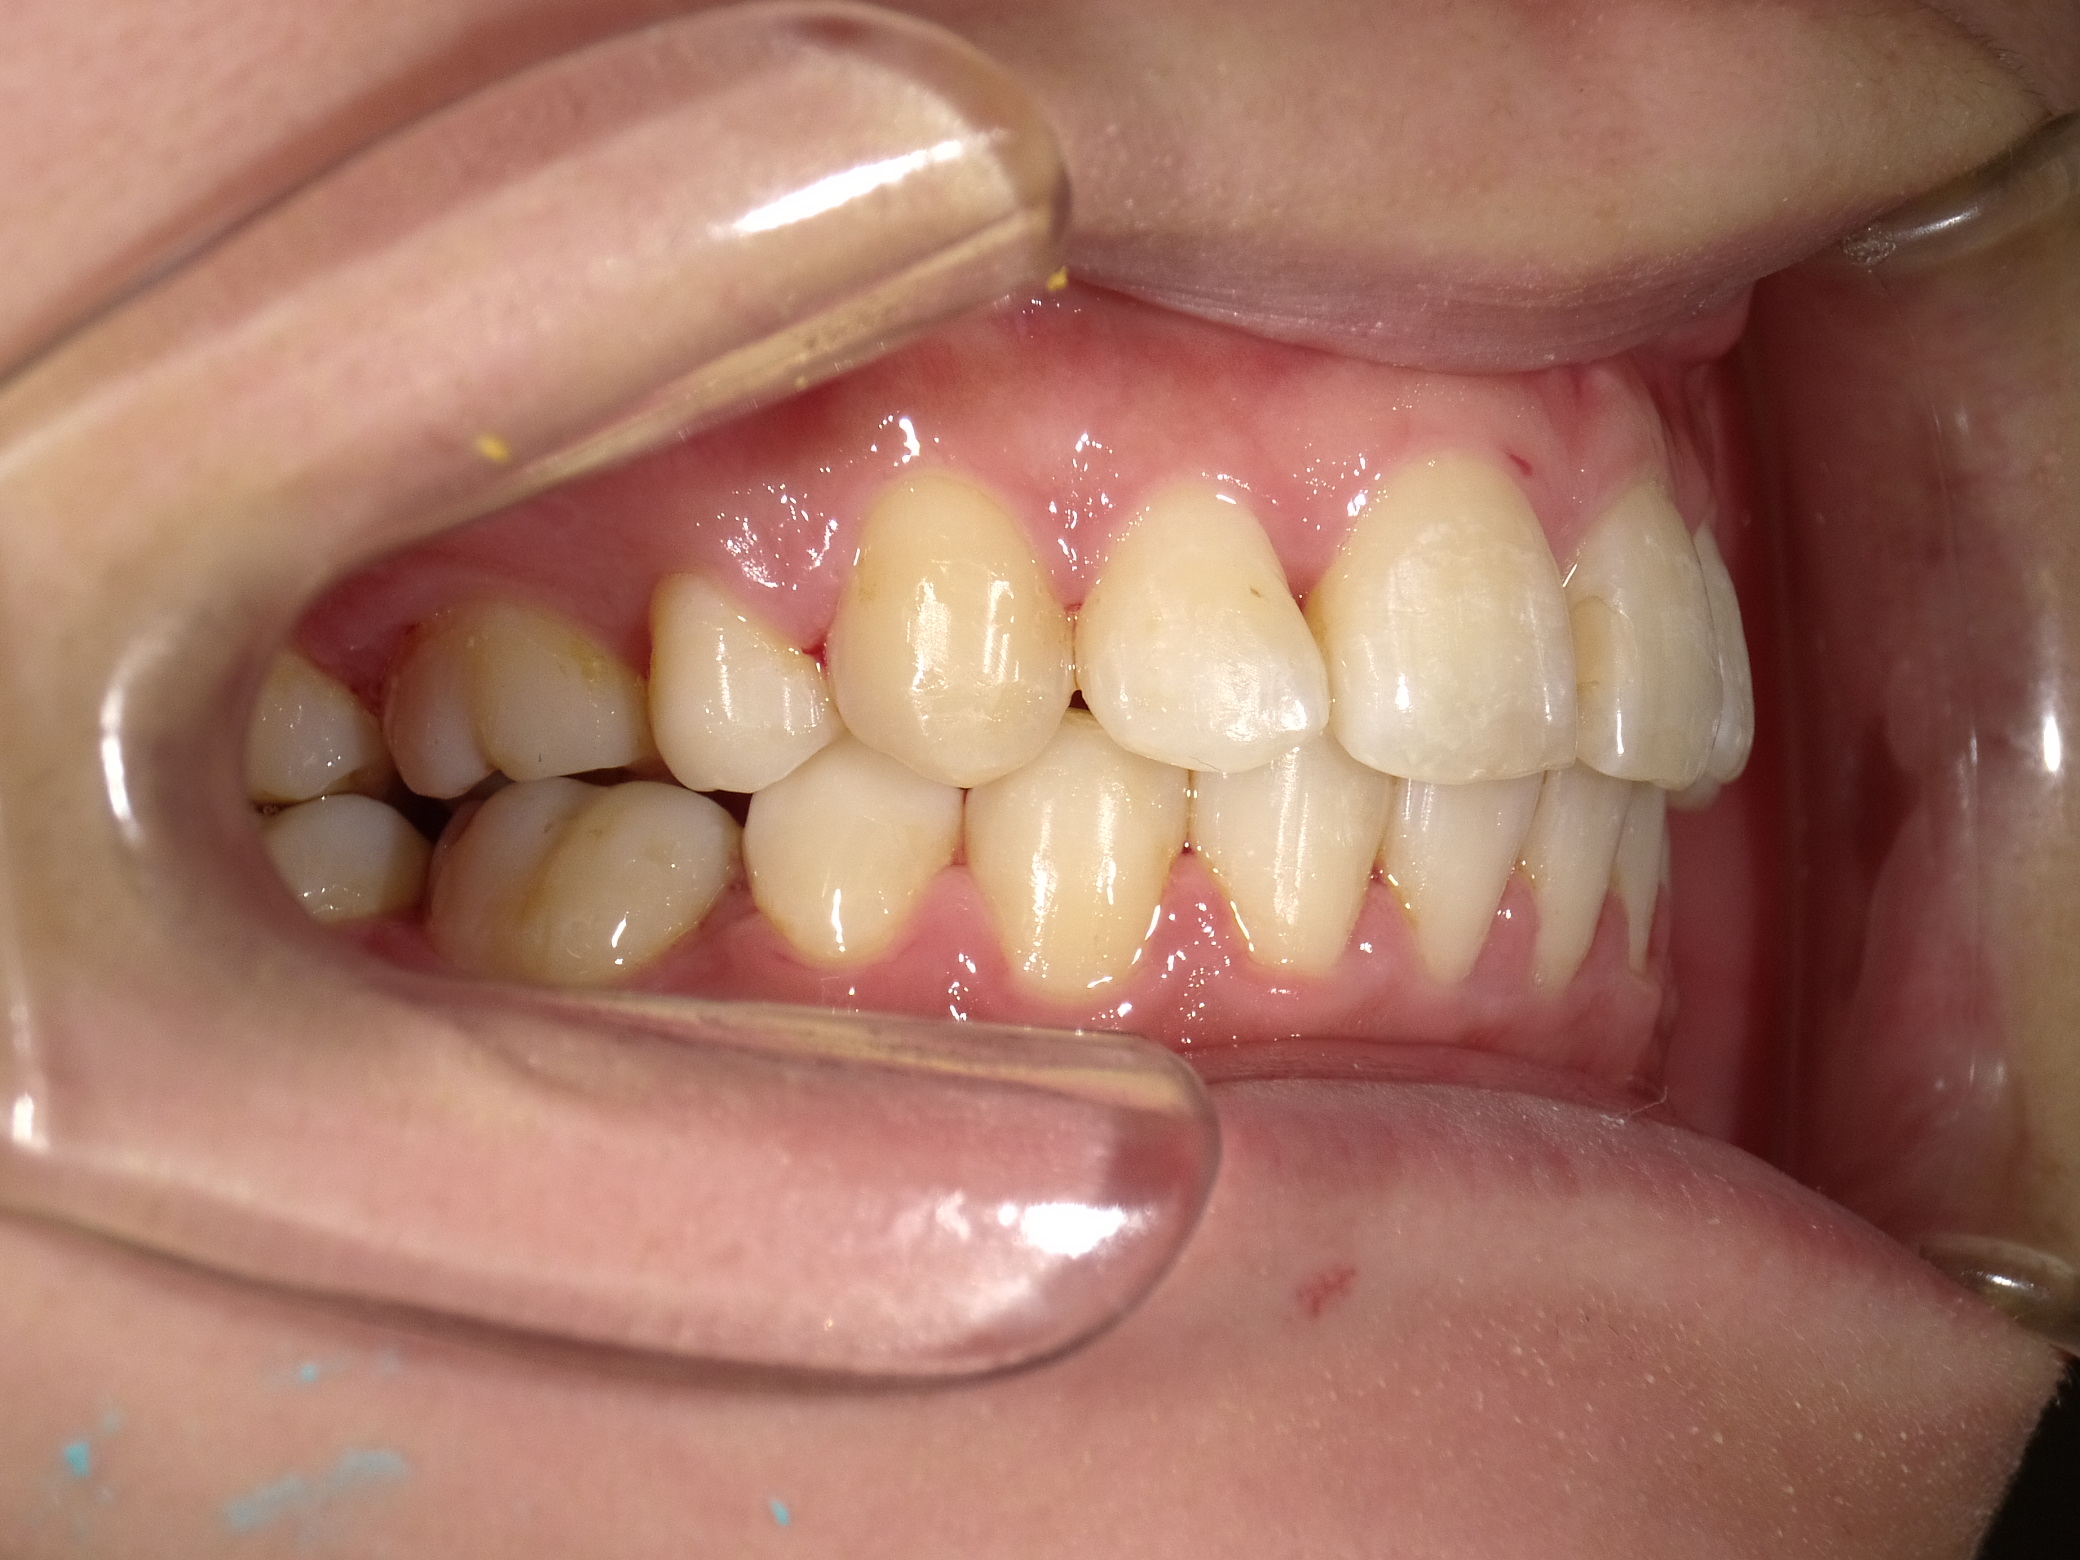

| 治療期間 | 2021年1月27日 〜2022年10月16日 |

|---|---|

| 治療費用 | 約770,000円 |

| 抜歯有無 | 抜歯なし |

| 矯正箇所 | クリアブラケット矯正 |